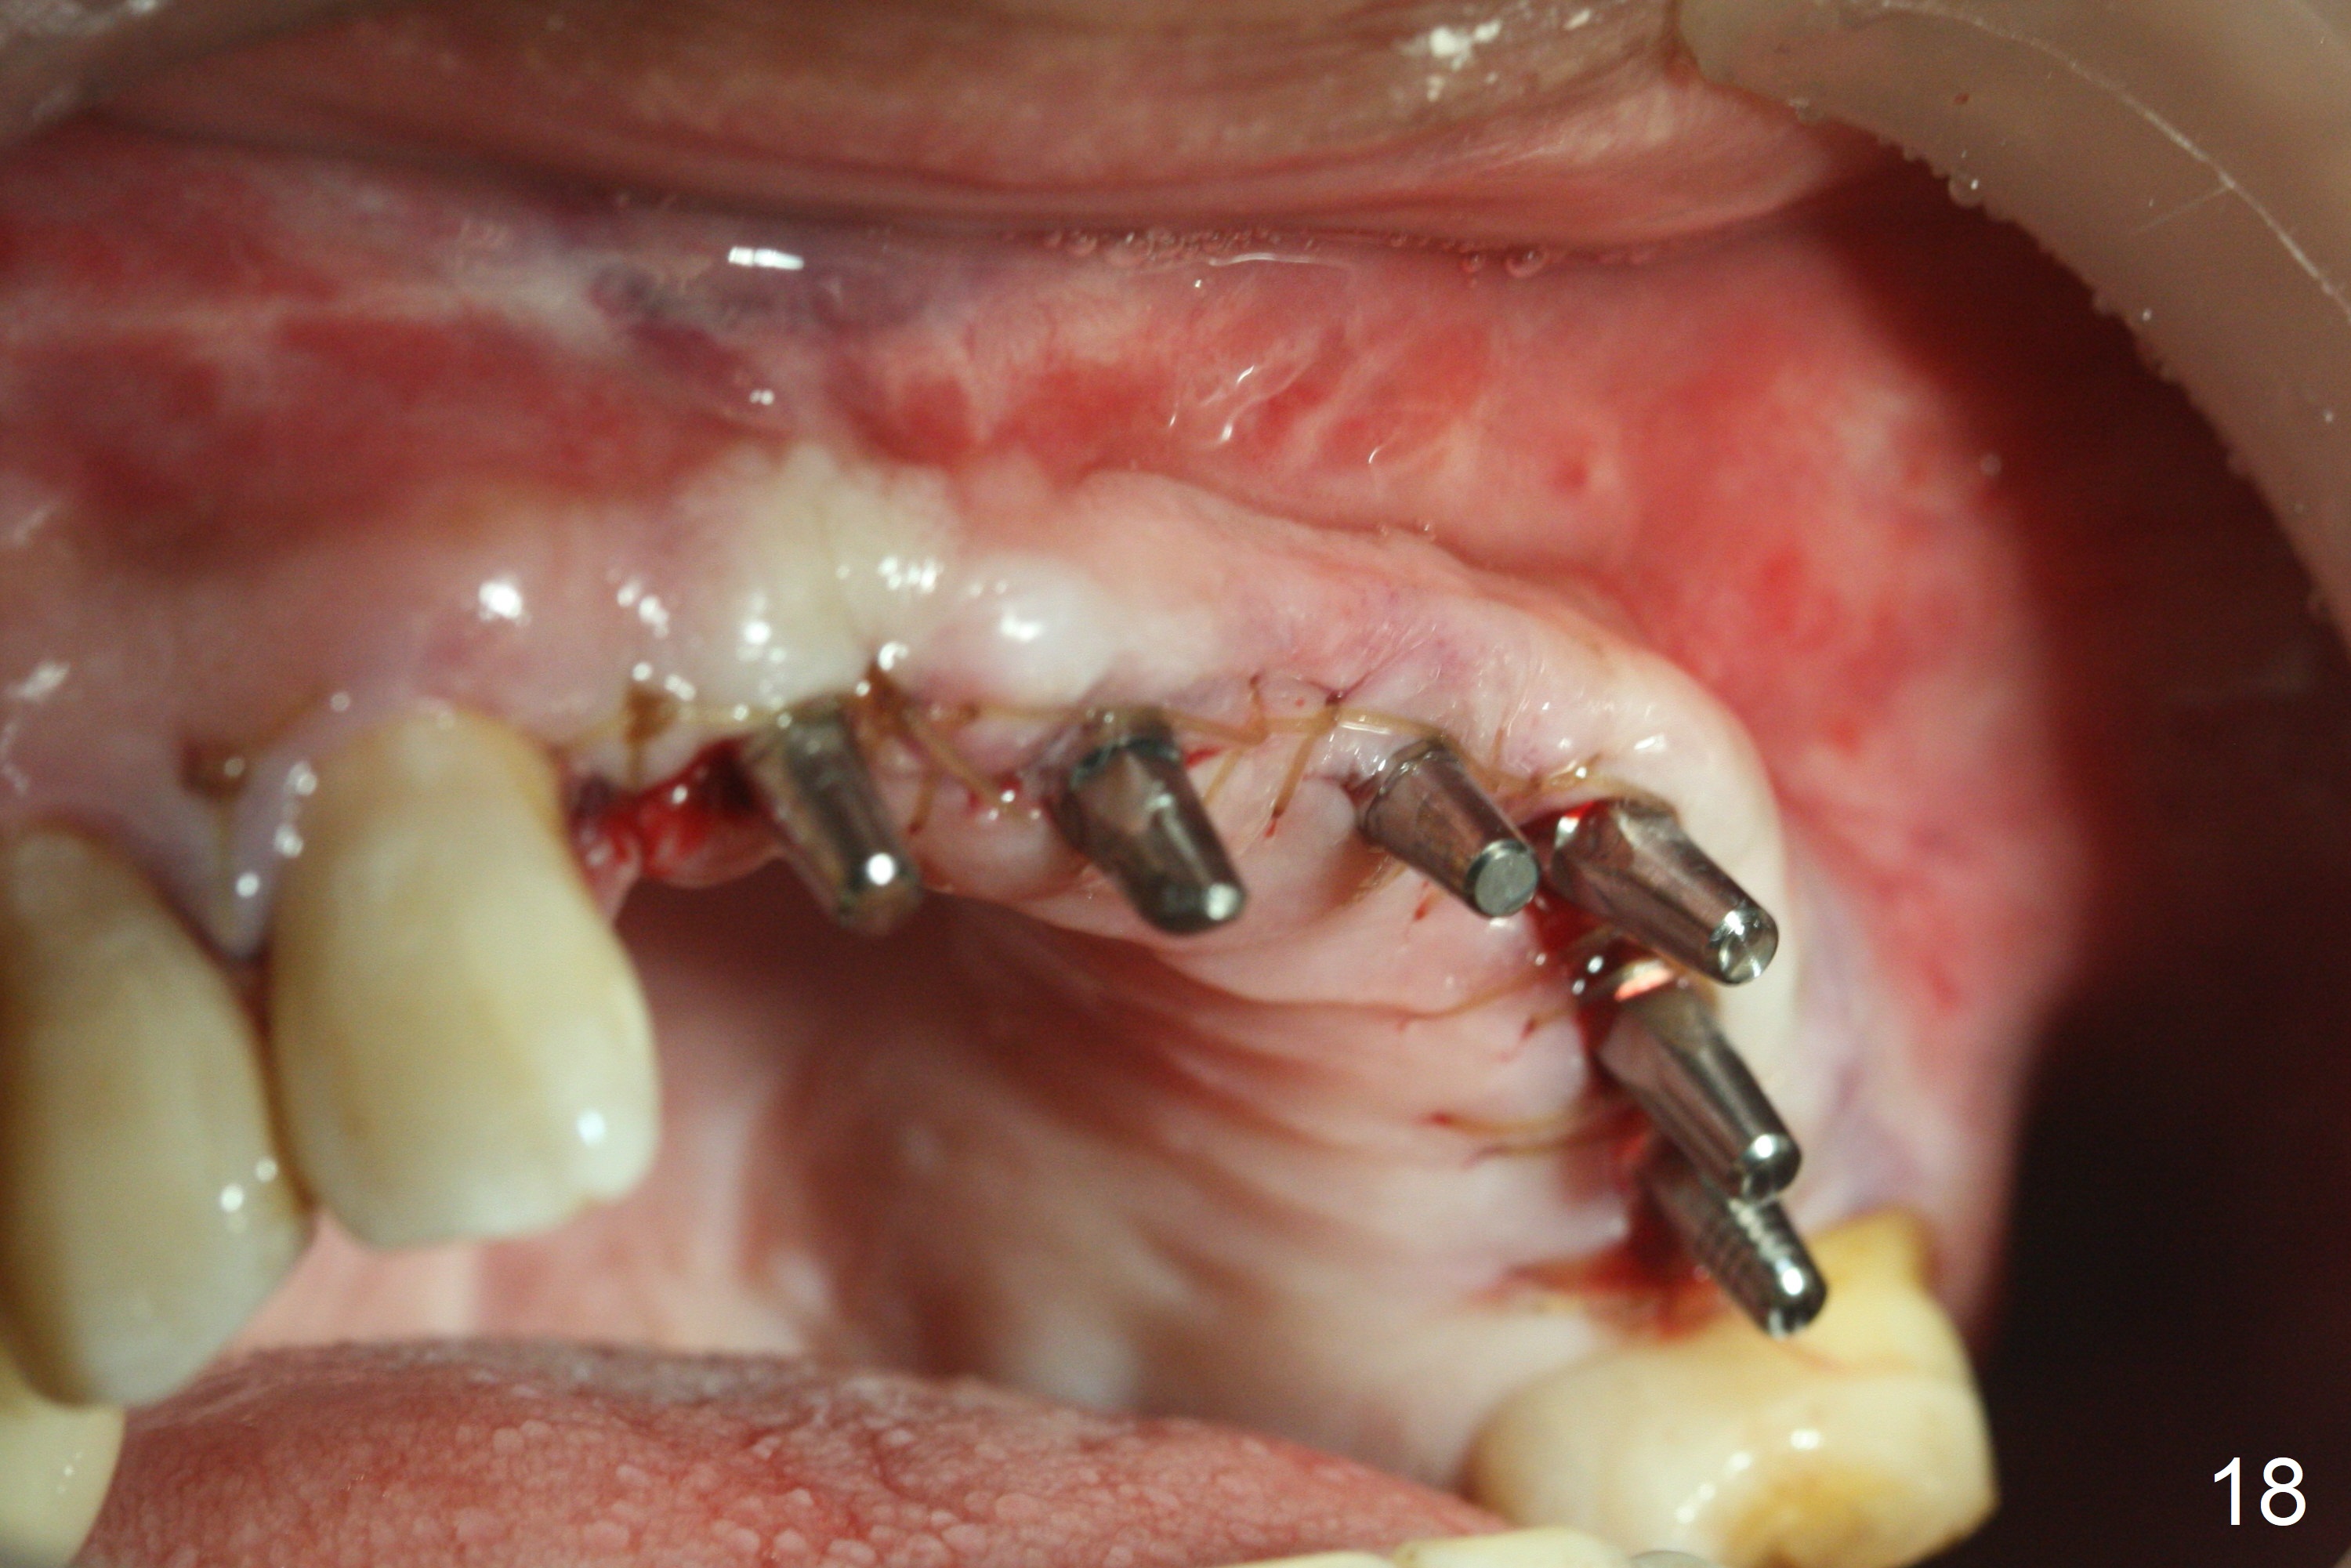

Following allograft placement around the implants (particularly palatally and in void due to change in osteotomy position) and PRF membrane buccopalatally, the ridge looks wider (Fig.17, 18) than preop (Fig.1). Note scar tissue in the upper labial vestibule (history of trauma). Continuous mattress suturing provides good wound closure.